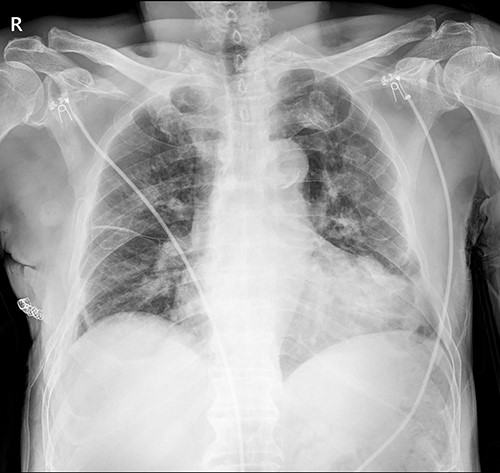

The patient visited the outpatient clinic on 07 March 2022, for stitches removal, complaining of mild discomfort on the operation site (Fig. 3.). Chest X-ray showed a large, localized submuscular emphysema between the rib cage and the SAM. The surgical wound was clear. Stitches were removed as planned, and the patient was asked to revisit the outpatient clinic 3 days later.